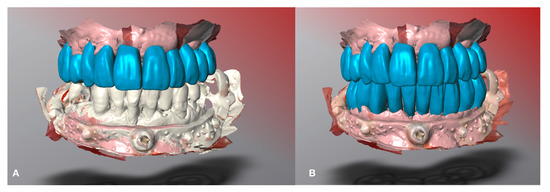

Interim superior restoration was computer-aided designed using presurgical occlusal plane as a reference. Interim inferior restoration was designed using the superior virtual interim restoration as a reference (Figure 9).

Figure 9. Restoration design. (A) Maxillary computer-aided restoration designed. (B) Design of the mandibular computer-aided restoration.